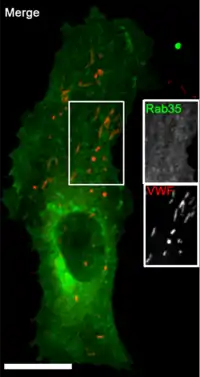

El cuerpo de Weibel-Palade es un orgánulo citoplasmático de las células endoteliales con forma de bastón.

Es un componente citoplasmático en forma de "varilla", que consiste en un haz de túbulos finos, envuelto por una sola membrana bien ajustada.

Los cuerpos de Weibel-Palade (WPB) tienen aproximadamente 0,1-0,3 micrómetro (μm) de grosor, miden hasta 3 μm de longitud.

Los WPB contienen varios túbulos pequeños, de ∼15 nanómetros (nm) de grosor, incrustados en una matriz densa y dispuestos paralelos al eje largo de la varilla. Tiene localización única en las células endoteliales de los vertebrados.[1]

Los cuerpos de Weibel-Palade (WPB) nacen en la Red del trans Golgi donde brotan en forma de estructuras discernibles. Sus dimensiones y morfología únicas, están dictadas por la carga principal el factor VWF, una glucoproteína grande. Luego, el factor VWF se transporta al Golgi donde se ensambla en cuantos definidos.

Los WPB se transportan a la periferia celular a lo largo de los microtúbulos; maduran para producir finalmente los orgánulos en forma de cigarro alargados que se encuentran en la periferia de las células endoteliales.